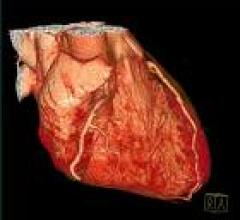

The importance of dealing with the epidemic of coronary artery disease (CAD) is well known, and the tools at our…

February 2, 2010 - Among noninvasive imaging tests for ruling out coronary artery disease (CAD), computed tomography…